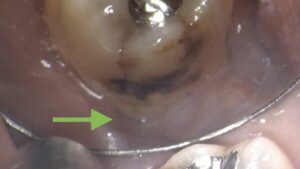

こちらが実際の手術時の写真です。

黒くなっているところは虫歯、

その下のモヤモヤしている部分が歯ぐきの中に付いている歯石です。

歯石を取り去った後の写真です。

根の表面が見えてキレイになっているのがわかります。